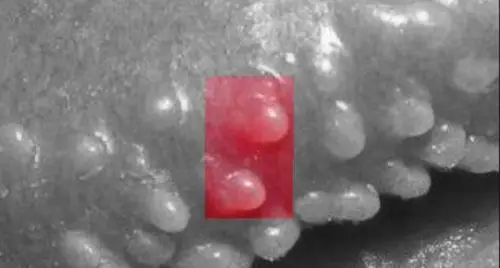

这种"丘疹" 比较小,在1毫米到3毫米左右,颜色为珍珠色或肉色,表面光滑